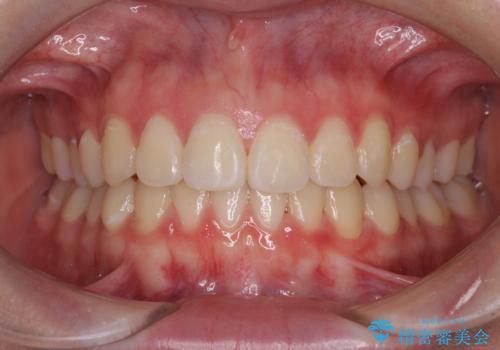

矯正治療が終わるタイミングに合わせてインプラントの埋入を行っていたので、矯正治療を終了すると同時にセラミック補綴治療を行えました。

短期間でしっかりと治療を終えることができました。